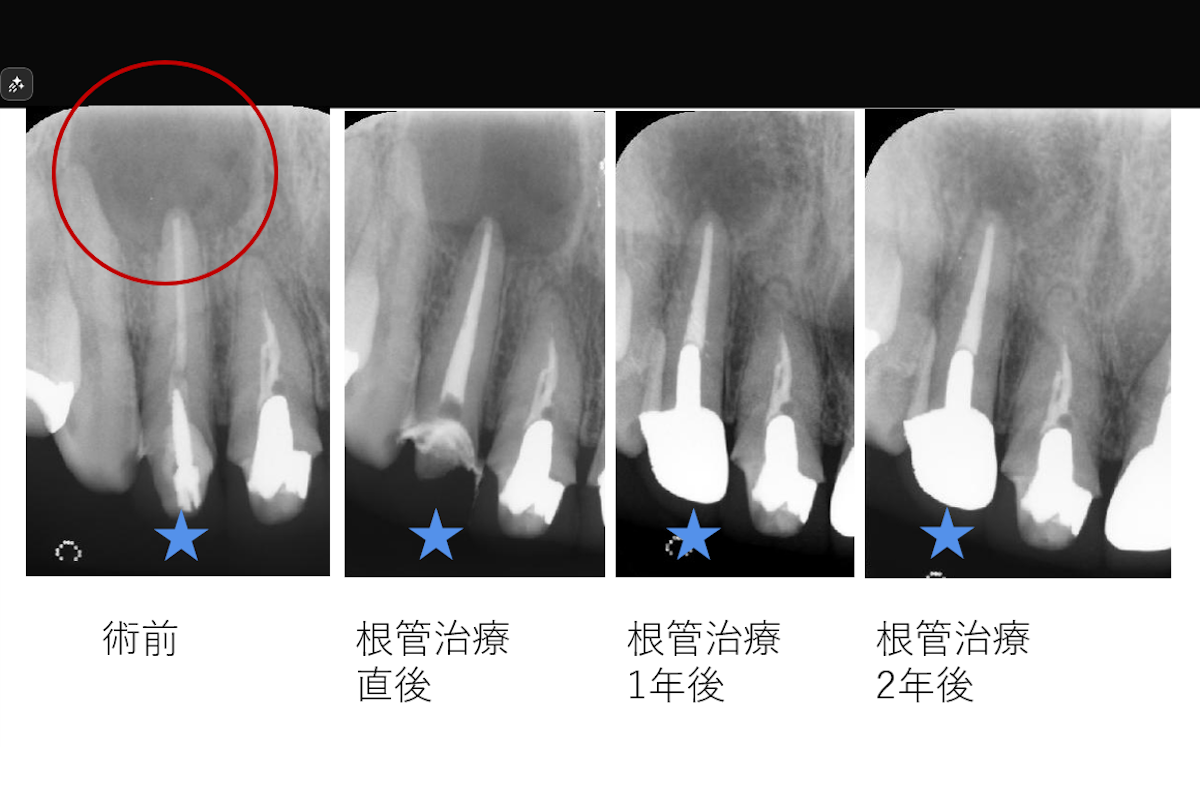

【約15mmの根尖病変を非外科的根管治療で治癒した症例】「歯茎を押すと痛い、他院で抜歯と言われた。」

「歯茎を押すと痛い、他院で抜歯と言われた。」ということで来院された患者様の症例です。

- 約15mmの根尖病変を非外科的根管治療で治癒した症例

- 治療内容: 上顎右側側切歯 根管治療(MTAを用いた根管充填)